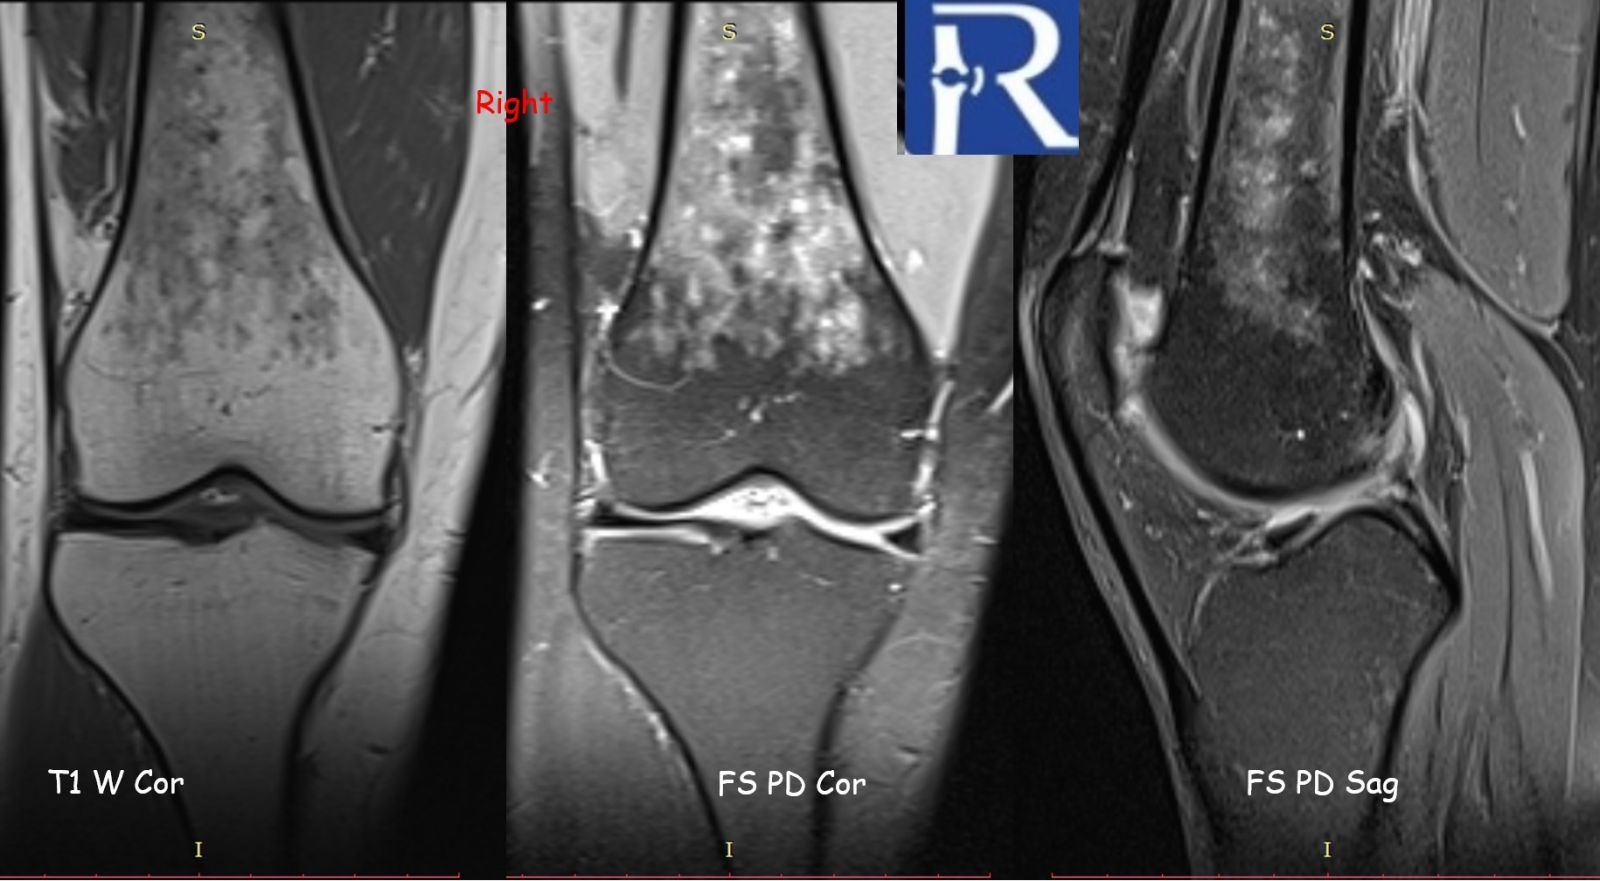

Initial plain radiographs of both knees were unremarkable. However, further evaluation with magnetic resonance imaging (MRI) revealed subcubic lesions infiltrating the bone marrow of both femurs, demonstrated on T1-weighted and fat-suppressed proton density sequences. Given the patient’s prior diagnosis of sarcoidosis, the imaging findings were interpreted as consistent with osseous involvement of the disease.

MRI is the most sensitive imaging modality for detecting skeletal sarcoidosis, particularly for evaluating changes in the bone marrow. However, the imaging appearance is nonspecific and may mimic other pathologies such as metastatic disease, lymphoma, multiple myeloma, or osteomyelitis. Correlation with clinical history and, when necessary, histopathologic confirmation is essential for accurate diagnosis.